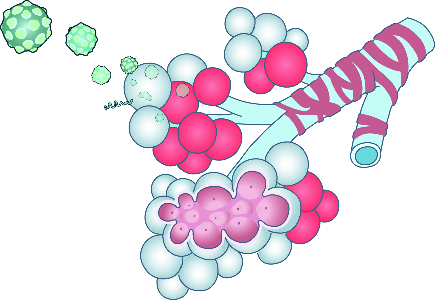

Detailreiche Fotografien aus der medizinischen Praxis ergänzen die Texte; moderne, genaue,

wissenschaftliche Zeichnungen geben Einblick in die Anatomie und die Funktion der Lunge und

anderer Organe.